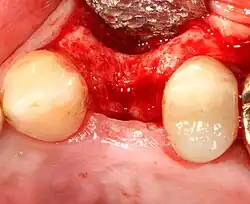

- Soft tissue reflection: An incision is made over the crest of bone, splitting the thicker attached gingiva roughly in half so that the final implant will have a thick band of tissue around it. The edges of tissue, each referred to as a flap, are pushed back to expose the bone. Flapless surgery is an alternate technique, where a small punch of tissue (the diameter of the implant) is removed for implant placement rather than raising flaps.

An increasingly common strategy to preserve bone and reduce treatment times includes the placement of a dental implant into a recent extraction site. On the one hand, it shortens treatment time and can improve aesthetics because the soft tissue envelope is preserved. On the other hand, implants may have a slightly higher rate of initial failure. Conclusions on this topic are difficult to draw, however, because few studies have compared immediate and delayed implants in a scientifically rigorous manner.[55]

Additional procedures to augment deficient bone in implant site

For an implant to osseointegrate, it needs to be surrounded by a healthy quantity of bone. In order for it to survive long-term, it needs to have a thick healthy soft tissue (gingiva) envelope around it. It is common for either the bone or soft tissue to be so deficient that the surgeon needs to reconstruct it either before or during implant placement.[50]: 1084 All techniques of augmenting the alveolar bone in preparation for implant placement are invasive and associated with a degree of morbidity.[59]